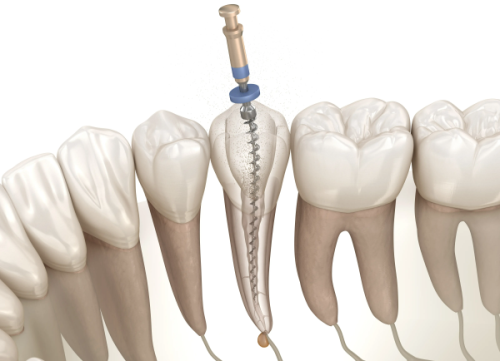

牙髓病诊疗:能够精细判断各类牙髓病症,采用合适的治疗方案,缓解患者牙齿疼痛等不适,修复牙齿正常功能。